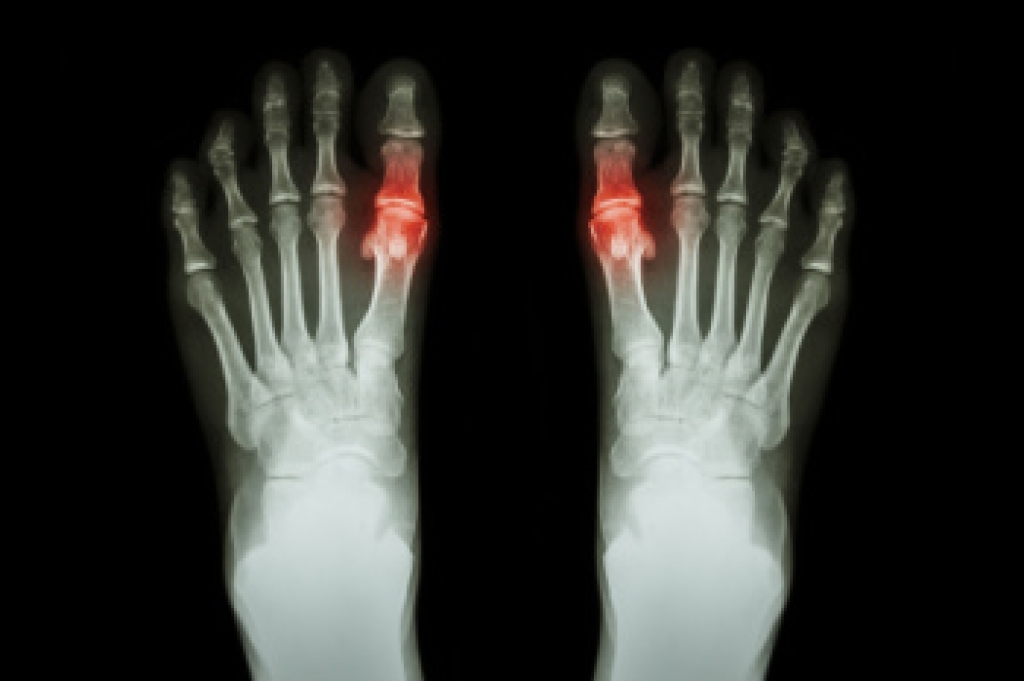

Hammertoe is a foot deformity that affects the joints of the second, third, fourth, or fifth toes of your feet. It is a painful foot condition in which these toes curl and arch up, which can often lead to pain when wearing footwear.

Hammertoe is a foot deformity in which one or more of the smaller toes bend abnormally at the middle joint, creating a curled or hammer-like appearance. This condition often develops gradually and can become rigid over time if not treated. Common causes include an imbalance in the muscles or tendons that control toe movement, often triggered by wearing tight or ill-fitting shoes that crowd the toes. Repeated pressure and friction can worsen the deformity. Risk factors include having a longer second toe, certain inherited foot structures, or conditions such as arthritis and diabetes. Wearing high heels or shoes with narrow toe boxes may also increase the likelihood of developing hammertoe. If you have signs of hammertoe, it is suggested that you are under the care of a podiatrist who can offer effective relief and treatment methods.